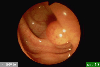

Various benign submucosal tumors and submucosal-tumor like lesions.

Endoscopy